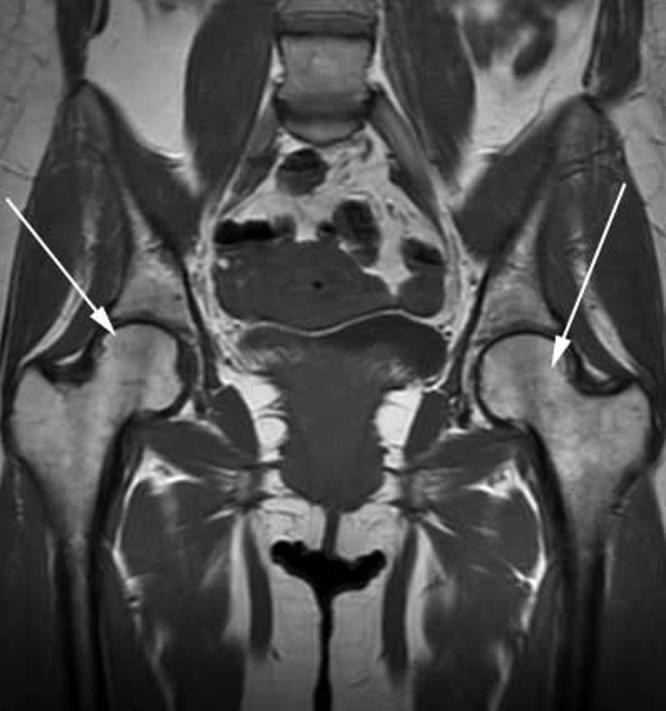

A 34-year-old Caucasian female presented during the third trimester of her pregnancy with bilateral hip pain that became progressively severe. Imaging of her pelvis and bilateral hips with MRI obtained during her third trimester of pregnancy demonstrated bilateral bone-marrow edema of the femoral heads and the sacrum at S1. Repeat MRI performed at 6 months postpartum revealed resolution of edema. MRI is considered the best diagnostic test for this condition in regards to sensitivity and specificity.

一名34岁的白种女性在妊娠晚期出现双侧髋部疼痛,且疼痛逐渐加重。在她妊娠晚期进行的骨盆及双侧髋部MRI检查显示双侧股骨头及骶骨S1处骨髓水肿。产后6个月复查MRI显示水肿消退。就敏感性和特异性而言,MRI被认为是诊断这种疾病的最佳检查方法。